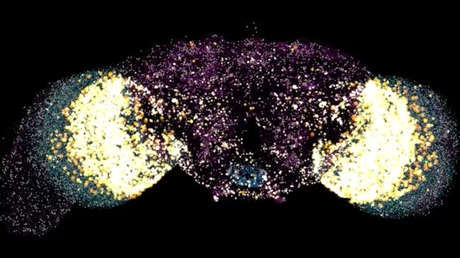

Científicos de todo el mundo unifican criterios para determinar el diagnóstico de muerte cerebral 16 ago 2020, 09:54 GMT